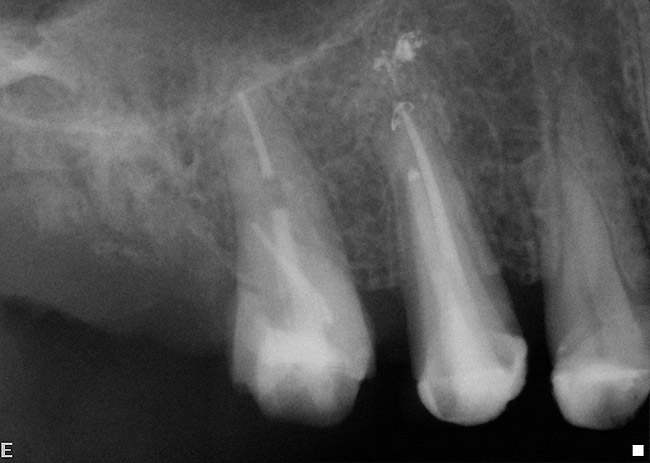

Figure 15  After extraction, the outline of the socket is  visualized radiographically.

Figure 15

Figure 16  Radiograph showing the site after it was filled with the resorbable bone graft material and covered with the PTFE barrier.

Figure 16

Figure 17  At the time of reentry, the pure-phase β-TCP particles appeared clinically to have resorbed, preserved the full ridge width, and been replaced by bone.

Figure 17